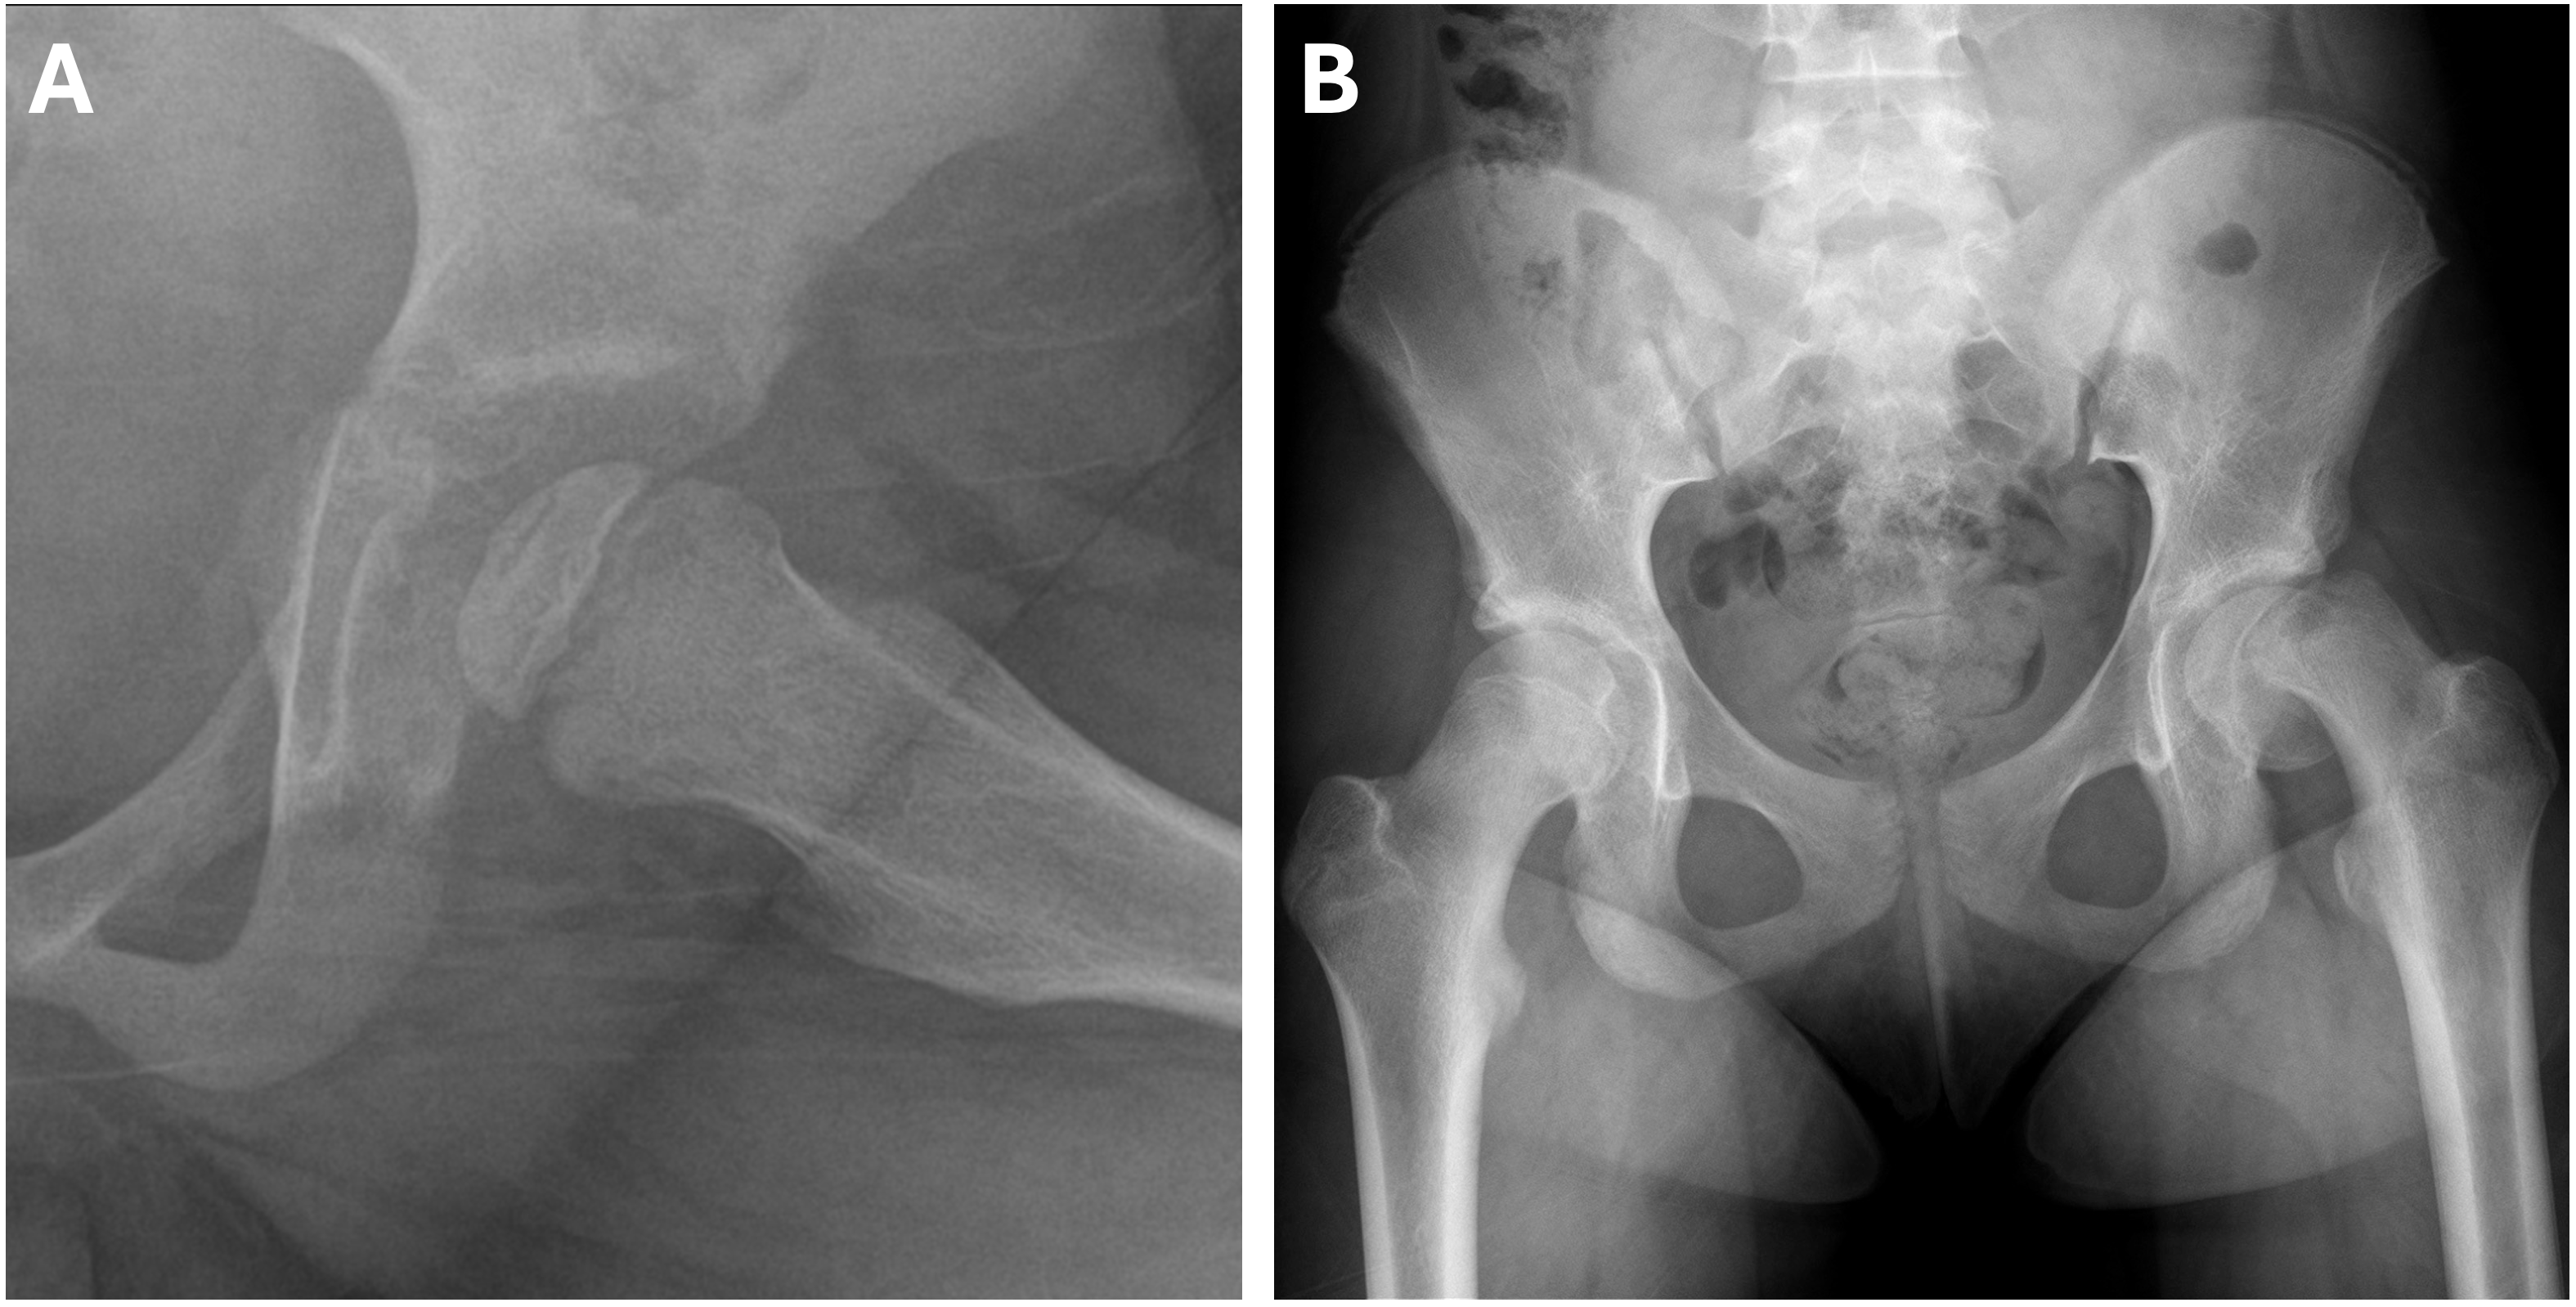

Zwei mal linksseitige Hüftschmerzen bei pädiatrischen Patienten. Was ist was?